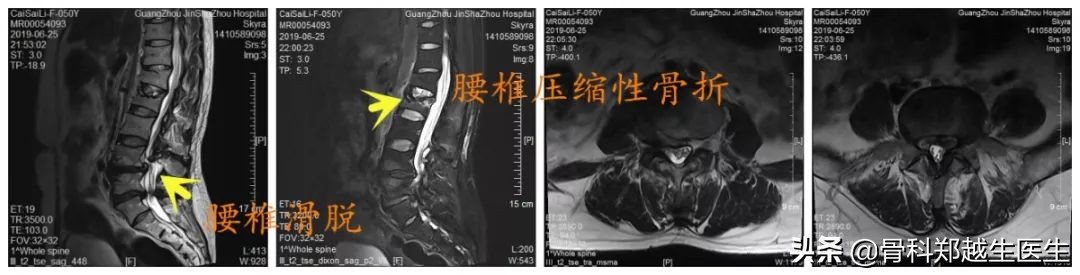

入院后体查:肚脐以下皮肤浅感觉减退,腰椎后凸畸形,L2椎体压痛、叩痛(+),L4-L5棘突间触及台阶感,直腿抬高试验(-),股神经牵拉试验(-),双下肢膝腱、跟腱反射正常,病理征(-)。

影像学检查提示:L2椎体压缩性骨折,L4椎体峡部裂并椎体滑移,T1椎体层面椎管内肿瘤。

患者诊断明确后,在我科行三期手术治疗,第一期,行腰椎经皮椎体成形术,术后腰部疼痛缓解,可坐起、站立行走。第二期,颈椎后路椎管内肿瘤摘除术,术后四肢麻木明显改善,肢体活动功能改善。第三期,腰椎后路椎间植骨融合椎弓根钉内固定术,术后患者可长时间站立、行走,生活基本恢复正常。